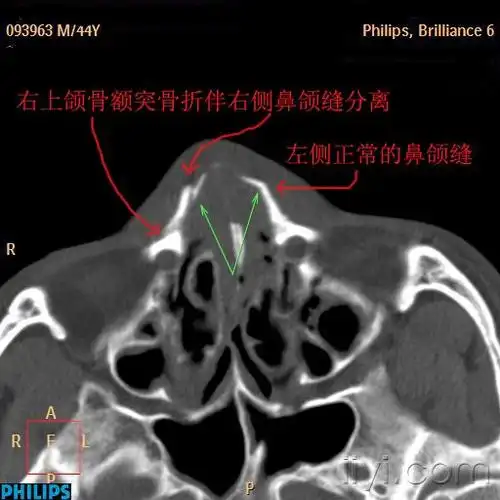

右侧上颌骨额突及鼻骨骨折是否构成轻伤害